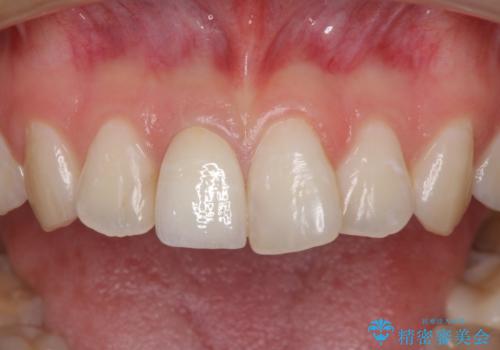

歯は神経をとると、だんだん黒くなることがあります。今回はセラミックで歯を覆うことにより、見た目の改善を図りました。

患者様のご希望で、最終的な色を決める前に、ホワイトニングをしました(約3万円)。ただし、ホワイトニング直後は色が白くなりすぎる等の恐れがあるため、色が落ち着くのを待ってからセラミックを製作しました。